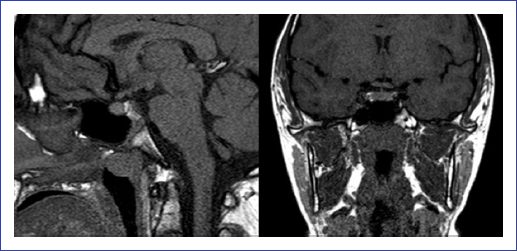

Hepatic ultrasound revealed hepatomegaly with fat deposition suggestive of moderate hepatic steatosis (Fig. 2) without splenomegaly. The family did not agree to perform a liver biopsy. No abnormal brain findings were shown by magnetic resonance imaging (Fig. 3). Thyroid gammagram with 131I and thyrotropin alpha stimulation (TSH = 43.26 mIU/l) was considered within the normal limits, and no data suggested residual thyroid tissue.

Figure 3 Magnetic resonance imaging in the pituitary region topography with no evidence of lesions occupying the space and glands with normal signal intensity.